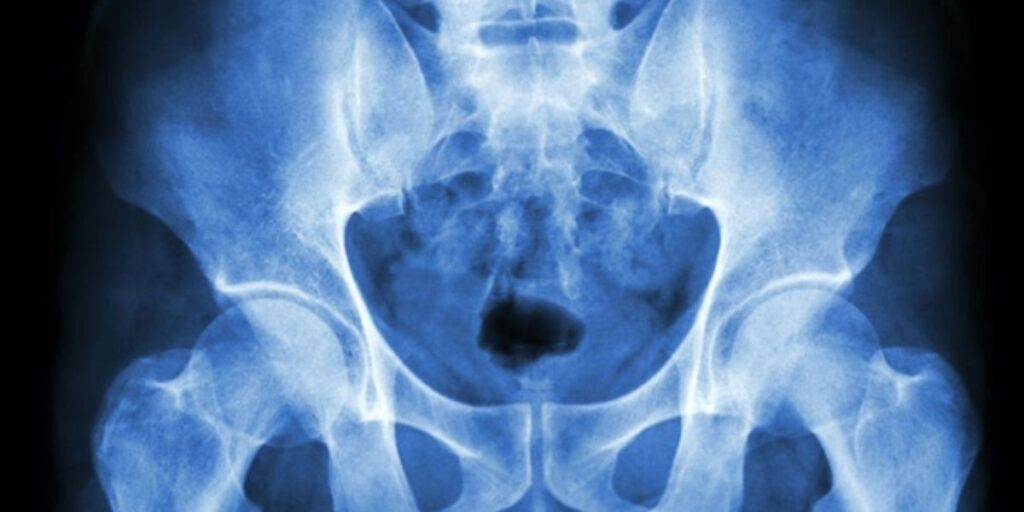

La Risonanza Magnetica Anca e Bacino è un esame diagnostico non invasivo, essenziale per ottenere immagini dettagliate e precise delle strutture anatomiche di queste regioni. Al Poliambulatorio S-Medical Group di Sora, l’esame viene eseguito utilizzando apparecchiature all’avanguardia e tecniche innovative, al fine di garantire diagnosi accurate e trattamenti personalizzati. In questa guida esploreremo tutti gli aspetti legati alla Risonanza Magnetica Anca e Bacino, incluse le sue finalità, il funzionamento, le patologie che può identificare e molto altro ancora.

La Risonanza Magnetica Anca e Bacino è una metodica di imaging che sfrutta l’interazione tra campi magnetici e onde radio per ottenere immagini ad alta risoluzione delle strutture interne dell’anca e del bacino. Questo esame consente ai medici del Poliambulatorio S-Medical Group di Sora di visualizzare in modo dettagliato le ossa, i muscoli, i tendini e le articolazioni, senza l’utilizzo di radiazioni ionizzanti. È un esame particolarmente indicato per diagnosticare condizioni come lesioni traumatiche, patologie articolari, infezioni e neoplasie.